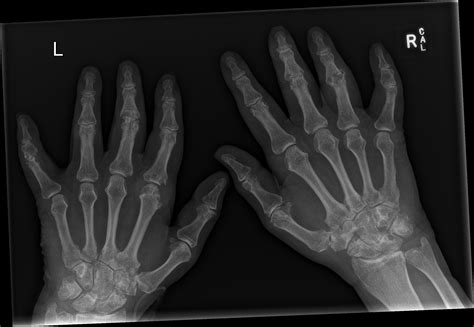

Differentiating Gout from Other Hand Conditions

It is easy to mistake gout in the hand for other conditions like osteoarthritis, rheumatoid arthritis, or even an infection. The following table highlights key differences to help you understand what might be occurring:

Condition Typical Onset Primary Symptoms

Gout Sudden (hours) Severe burning pain, redness, extreme tenderness.

Osteoarthritis Gradual (years) Dull ache, morning stiffness, bony nodes.

Rheumatoid Arthritis Gradual (weeks/months) Symmetrical joint swelling, fatigue, stiffness.

Infection Sudden Fever, chills, spreading redness, pus.